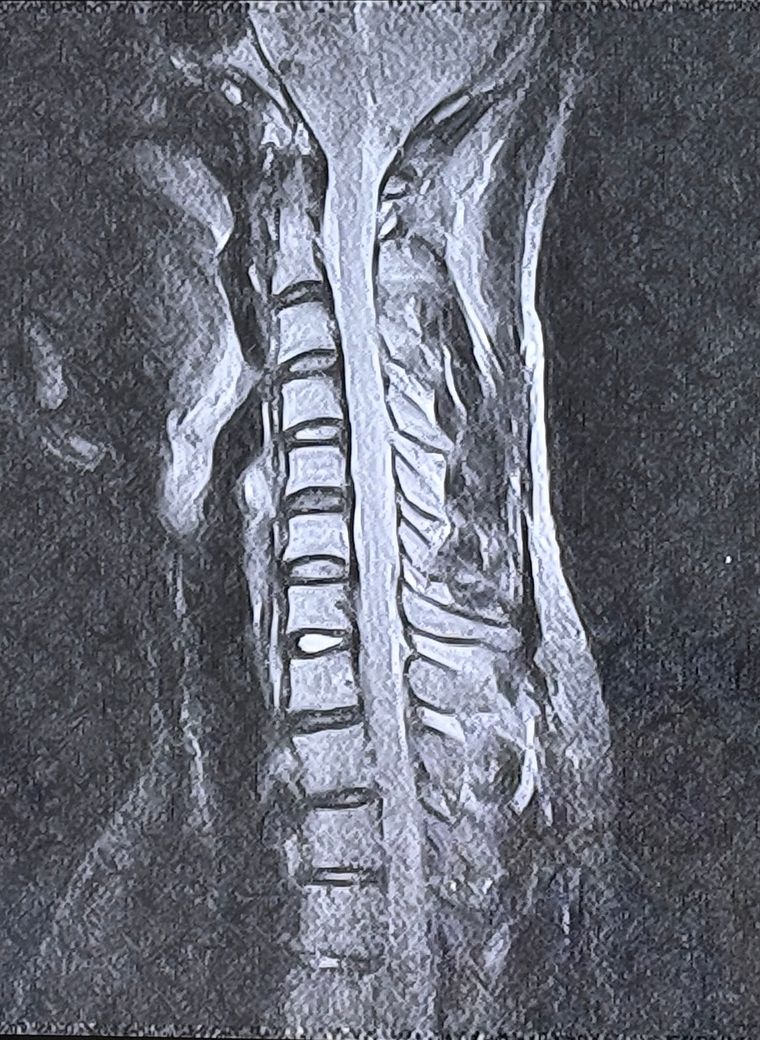

두번째 사진은 경추 6~7번인거같습니다

• 2번 째 사진

• 제공해주신 영상은 경추 MRI로 보이며, 전반적인 정렬은 유지되고 있고 C6–7에서 후방으로 디스크가 돌출된 소견은 확인됩니다. 다만 단일 컷 이미지로는 신경공 협착 정도나 신경근 압박의 정확한 정도를 정량적으로 판단하기는 제한이 있습니다. 척수 자체의 신호 변화는 뚜렷하게 보이지 않아 중증 척수병증 가능성은 낮아 보입니다.

병태생리 측면에서 C6–7 디스크는 C7 신경근을 자극하는 경우가 많고, 말씀하신 검지·중지 감각 이상, 상완 후면 통증, 견갑부 통증은 전형적인 경추 신경근병증 분포와 대체로 일치합니다. 단순한 “목을 젖힘” 동작 하나로도 기존에 약해져 있던 섬유륜이 순간적으로 더 벌어지면서 디스크 팽윤이 악화되어 증상이 유발되는 경우는 실제로 흔합니다.

신체 진찰과 추가적 영상의 확인이 필요하겠으나 올려주신 사진에서 신경 압박 소견은 저명하지 않습니다.

6-7번 디스크가 가볍게 밀려나온 상태라면, 신경을 완전히 짓누르는 탈출보다는 덜한 상태이지만 신경은 매우 예민해서 살짝 스치거나 염증 반응만 생겨도 지금처럼 손끝까지 증상이 나타날 수 있습니다.